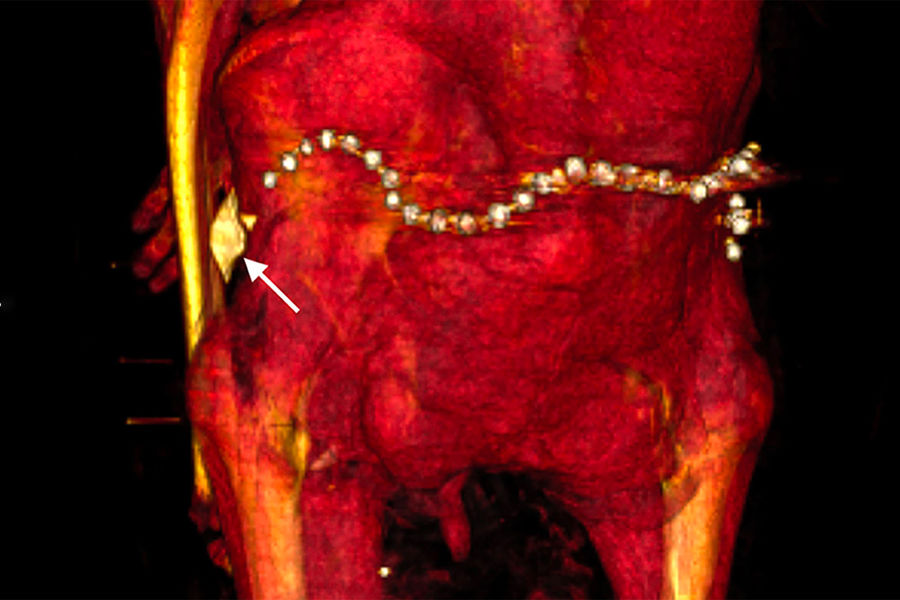

В бинтах исследователи также обнаружили около 30 украшений, в частности пояс из металлических (вероятно, золотых) бусин в задней части тазовой области, и фаянсовый амулет в форме раковины улитки у левого бедра.

Некоторые из украшений, вероятно, появились при повторном захоронении, считает Салим — так бальзамировщики хотели компенсировать ущерб, нанесенный грабителями.